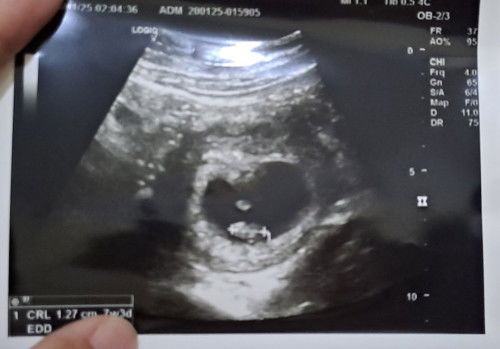

Bunda, apakah seperti ini hamil? Dari kemarin Senin, saya keluar flek tapi hanya sedikit banget. Baru kemarin Jumat keluar lebih banyak. Saya kira haid karena sakit perut juga seperti pas haid. Tapi kok nggak keluar-keluar darah haidnya? Coba tespek, hasilnya seperti itu. Tapi perut saya masih agak sakit, kurang enak badan juga. Di Miss v juga terasa lembab seperti saat haid. Terima kasih bunda ♥️#Sharing_dong_Bund